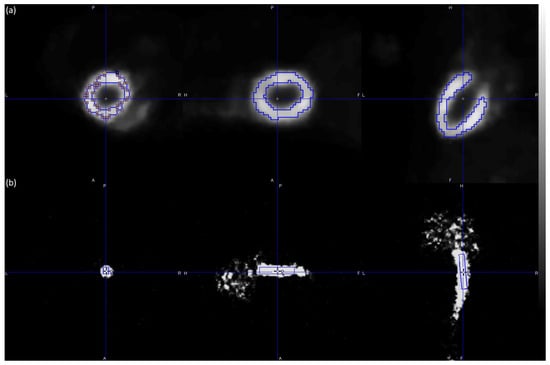

- Vrachliotis, A.; Kastis, G.A.; Protonotarios, N.E.; Fokas, A.S.; Nekolla, S.G.; Anagnostopoulos, C.D.; Costaridou, L.; Gaitanis, A. Evaluation of the spline reconstruction technique for preclinical PET imaging. Comput. Methods Programs Biomed. 2022, 217, 106668. [Google Scholar] [CrossRef]